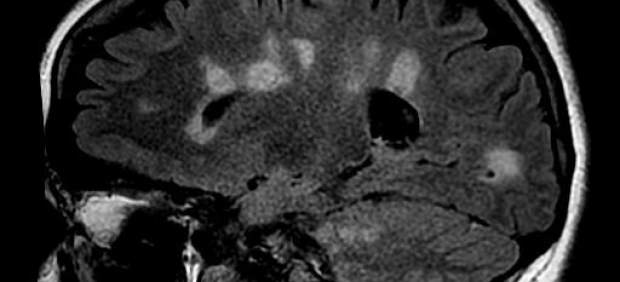

La esclerosis múltiple puede estar latente en tu cuerpo, generándose en tu cerebro o médula espinal, y no percatarte de sus daños hasta que se manifiesta en forma de brote, tal y como han experimentado numerosos afectados. Una pierna dormida de manera prolongada, visión doble, cefaleas continuas, incluso dificultades en el habla, hasta la inmovilidad total de algunas articulaciones del cuerpo y el mal funcionamiento de algún órgano son algunos de sus efectos.

Esta enfermedad autoinmune y neurodegenerativa desmielinizante provoca daños en la capa de mielina de las fibras nerviosas provocando un mal funcionamiento de órganos y músculos.

Durante muchos años ha sido considerada una enfermedad de sustancia blanca del sistema nervioso central aunque un número creciente de estudios haya demostrado que también afecta a la materia gris.

En la esclerosis múltiple se verifica un daño y una pérdida de mielina en varias áreas -de ahí el nombre de múltiple- del sistema nervioso central. Numerosas evidencias sean clínicas o experimentales indican que existe un proceso de desmielinización que determina daños o pérdida de la mielina y la formación de lesiones (placas).

Estas pueden cambiar de una fase inflamatoria inicial a una crónica, en la cual provoca características similares a las cicatrices, de ahí la denominación ‘esclerosis’, que significa «endurecimiento patológico de un órgano o tejido».